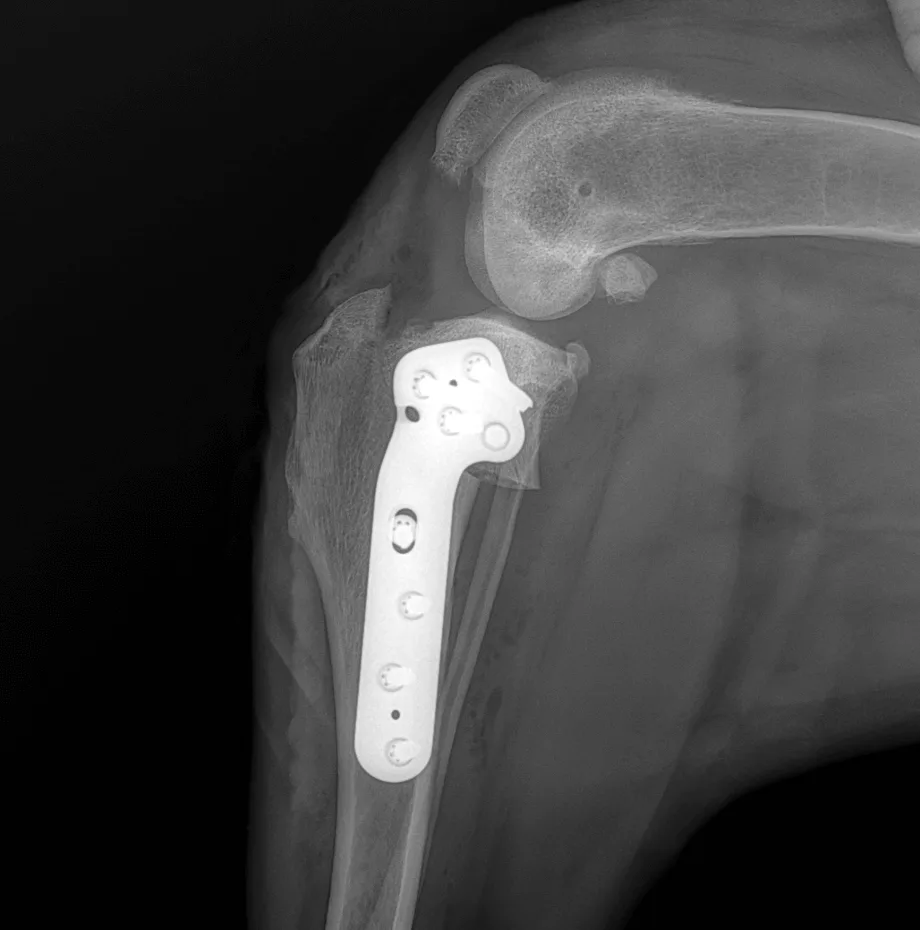

TPLO, Tibial Plateau Leveling Osteotomy

The slope of the tibial plateau is surgically altered so that the load axis of the knee changes. This neutralizes the stabilizing role of the front cruciate ligament without replacing it. Based on the growing body of objective studies, TPLO is the only method shown to restore load bearing to the level of the healthy limb. It is considered the international gold standard in cruciate surgery for dogs and is suitable for all sizes.

Postoperative X-ray image of the TPLO technique. The rotated tibial plateau, which is fixed with a special plate, can be seen.